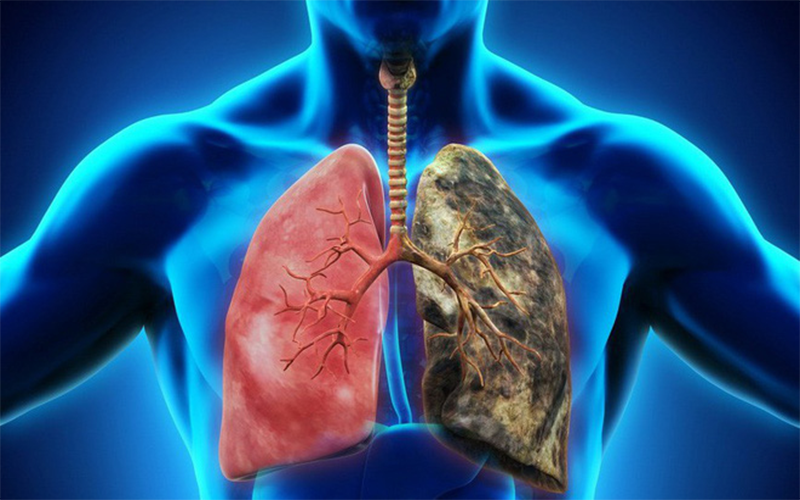

Chụp x quang cho thấy hình ảnh trực quan nhất của tim, phổi, mạch máu, xương sườn và xương của cột sống. Khi đến gặp bác sĩ với những cơn đau ngực hoặc khó thở, chụp x quang sẽ là chỉ định đầu tiên giúp xác định xem bạn có bị suy tim, phổi, viêm phổi, xương sườn bị gãy hoặc không khí tích tụ trong không gian xung quanh phổi (tràn khí màng phổi) hay không?

Chụp x quang tim phổi thẳng là phương pháp được sử dụng ở hầu hết các bệnh viện nhằm phát hiện những bất thường ở tim, phổi và các cơ quan lân cận mà mắt thường không thể thấy được.

- Các dấu hiệu bất thường ở phổi: Chụp x quang có thể phát hiện ung thư hoặc nhiễm trùng ở phổi.

- Vấn đề tim liên quan đến phổi: Chụp x quang có thể cho thấy sự thay đổi hoặc bất thường trong phổi xuất phát từ vấn đề về tim. Chất lỏng có thể tích tụ trong phổi (phù phổi).

- Kích thước của trái tim: Những thay đổi trong kích thước và hình dạng của trái tim có thể chỉ ra một điều kiện khác nhau, chẳng hạn như suy tim, bệnh tim bẩm sinh, chất lỏng xung quanh tim (tràn dịch màng ngoài tim), và các vấn đề với một hoặc nhiều van tim.

- Những phác thảo về các mạch lớn gần tim – động mạch chủ và động mạch và tĩnh mạch phổi – có thể nhìn thấy trên x quang, dựa vào phim, bác sĩ có thể nghi ngờ phình động mạch chủ hoặc các vấn đề mạch máu khác, hoặc bệnh tim bẩm sinh.

- Chụp x quang có thể phát hiện sự hiện diện của calcium trong trái tim hoặc mạch máu, từ đó có thể chỉ ra thiệt hại cho van tim, động mạch vành, cơ tim hoặc túi bảo vệ bao quanh. Canxi trong phổi có thể là dấu hiệu từ một bệnh nhiễm trùng cũ được giải quyết, hoặc một bệnh nghiêm trọng hơn mà bạn đã gặp phải.